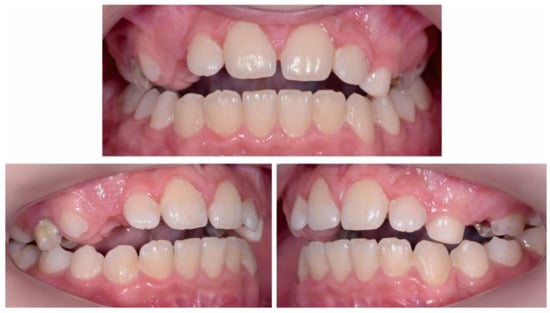

2.2.1. Initial Examination

2.2.2. Treatment Objectives